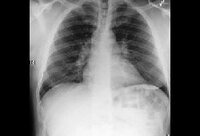

Pericardial tamponade: admission chest x-ray

Usalan C, Atalar E, Vural FK. Pericardial tamponade in a 65-year-old woman. Postgrad Med J. 1999;75:183-184; used with permission.